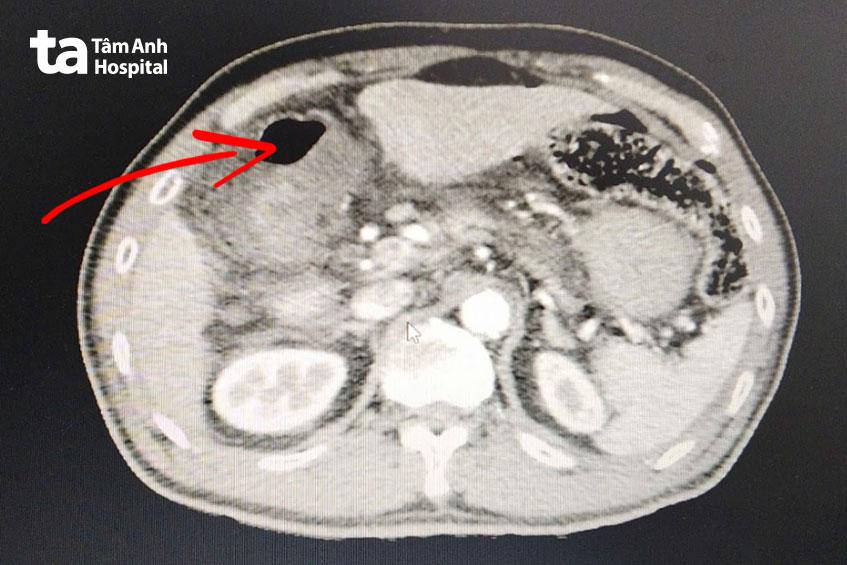

Ông Đấu được người nhà chuyển đến cấp cứu tại Bệnh viện Đa khoa Tâm Anh TP HCM. Ngày 26/11, bác sĩ chuyên khoa 1 Nguyễn Công Uẫn, Trung tâm Nội soi và Phẫu thuật Nội soi Tiêu hóa, cho biết kết quả chụp MSCT bụng (Multislice Computerized Tomography – chụp cắt lớp vi tính đa lát cắt) khẩn cấp cho thấy ông Đấu có dịch và hơi tự do ở ổ bụng, kèm thâm nhiễm mỡ, tụ dịch xung quanh hang môn vị dạ dày và hành tá tràng. Kết hợp các biểu hiện lâm sàng như bụng cứng, đau bụng dữ dội, mạch đập nhanh, thở nhanh…, bác sĩ Uẫn chẩn đoán ông Đấu bị viêm phúc mạc, nhiễm trùng ổ bụng do thủng tạng cần mổ cấp cứu khẩn cấp.

Ông Đấu được tiến hành phẫu thuật nội soi ngay trong đêm, cứu nguy tình trạng nhiễm trùng nặng. Trong quá trình phẫu thuật, bác sĩ nhận thấy ổ bụng có nhiều dịch mủ tập trung ở vị trí dưới và trên gan phải, dạ dày và hành tá tràng. Mặt trước phía bờ cong nhỏ dạ dày có lỗ thủng tròn đều kích thước 5 mm, đang trong tình trạng rỉ dịch tiêu hóa và dịch mật. Bác sĩ tiến hành hút rửa sạch ổ bụng bằng nước ấm nhiều lần cho đến khi nước trong. Sau đó, sinh thiết bờ lỗ thủng, khâu lại lỗ thủng, đắp mạc nối lớn lên vị trí thủng.